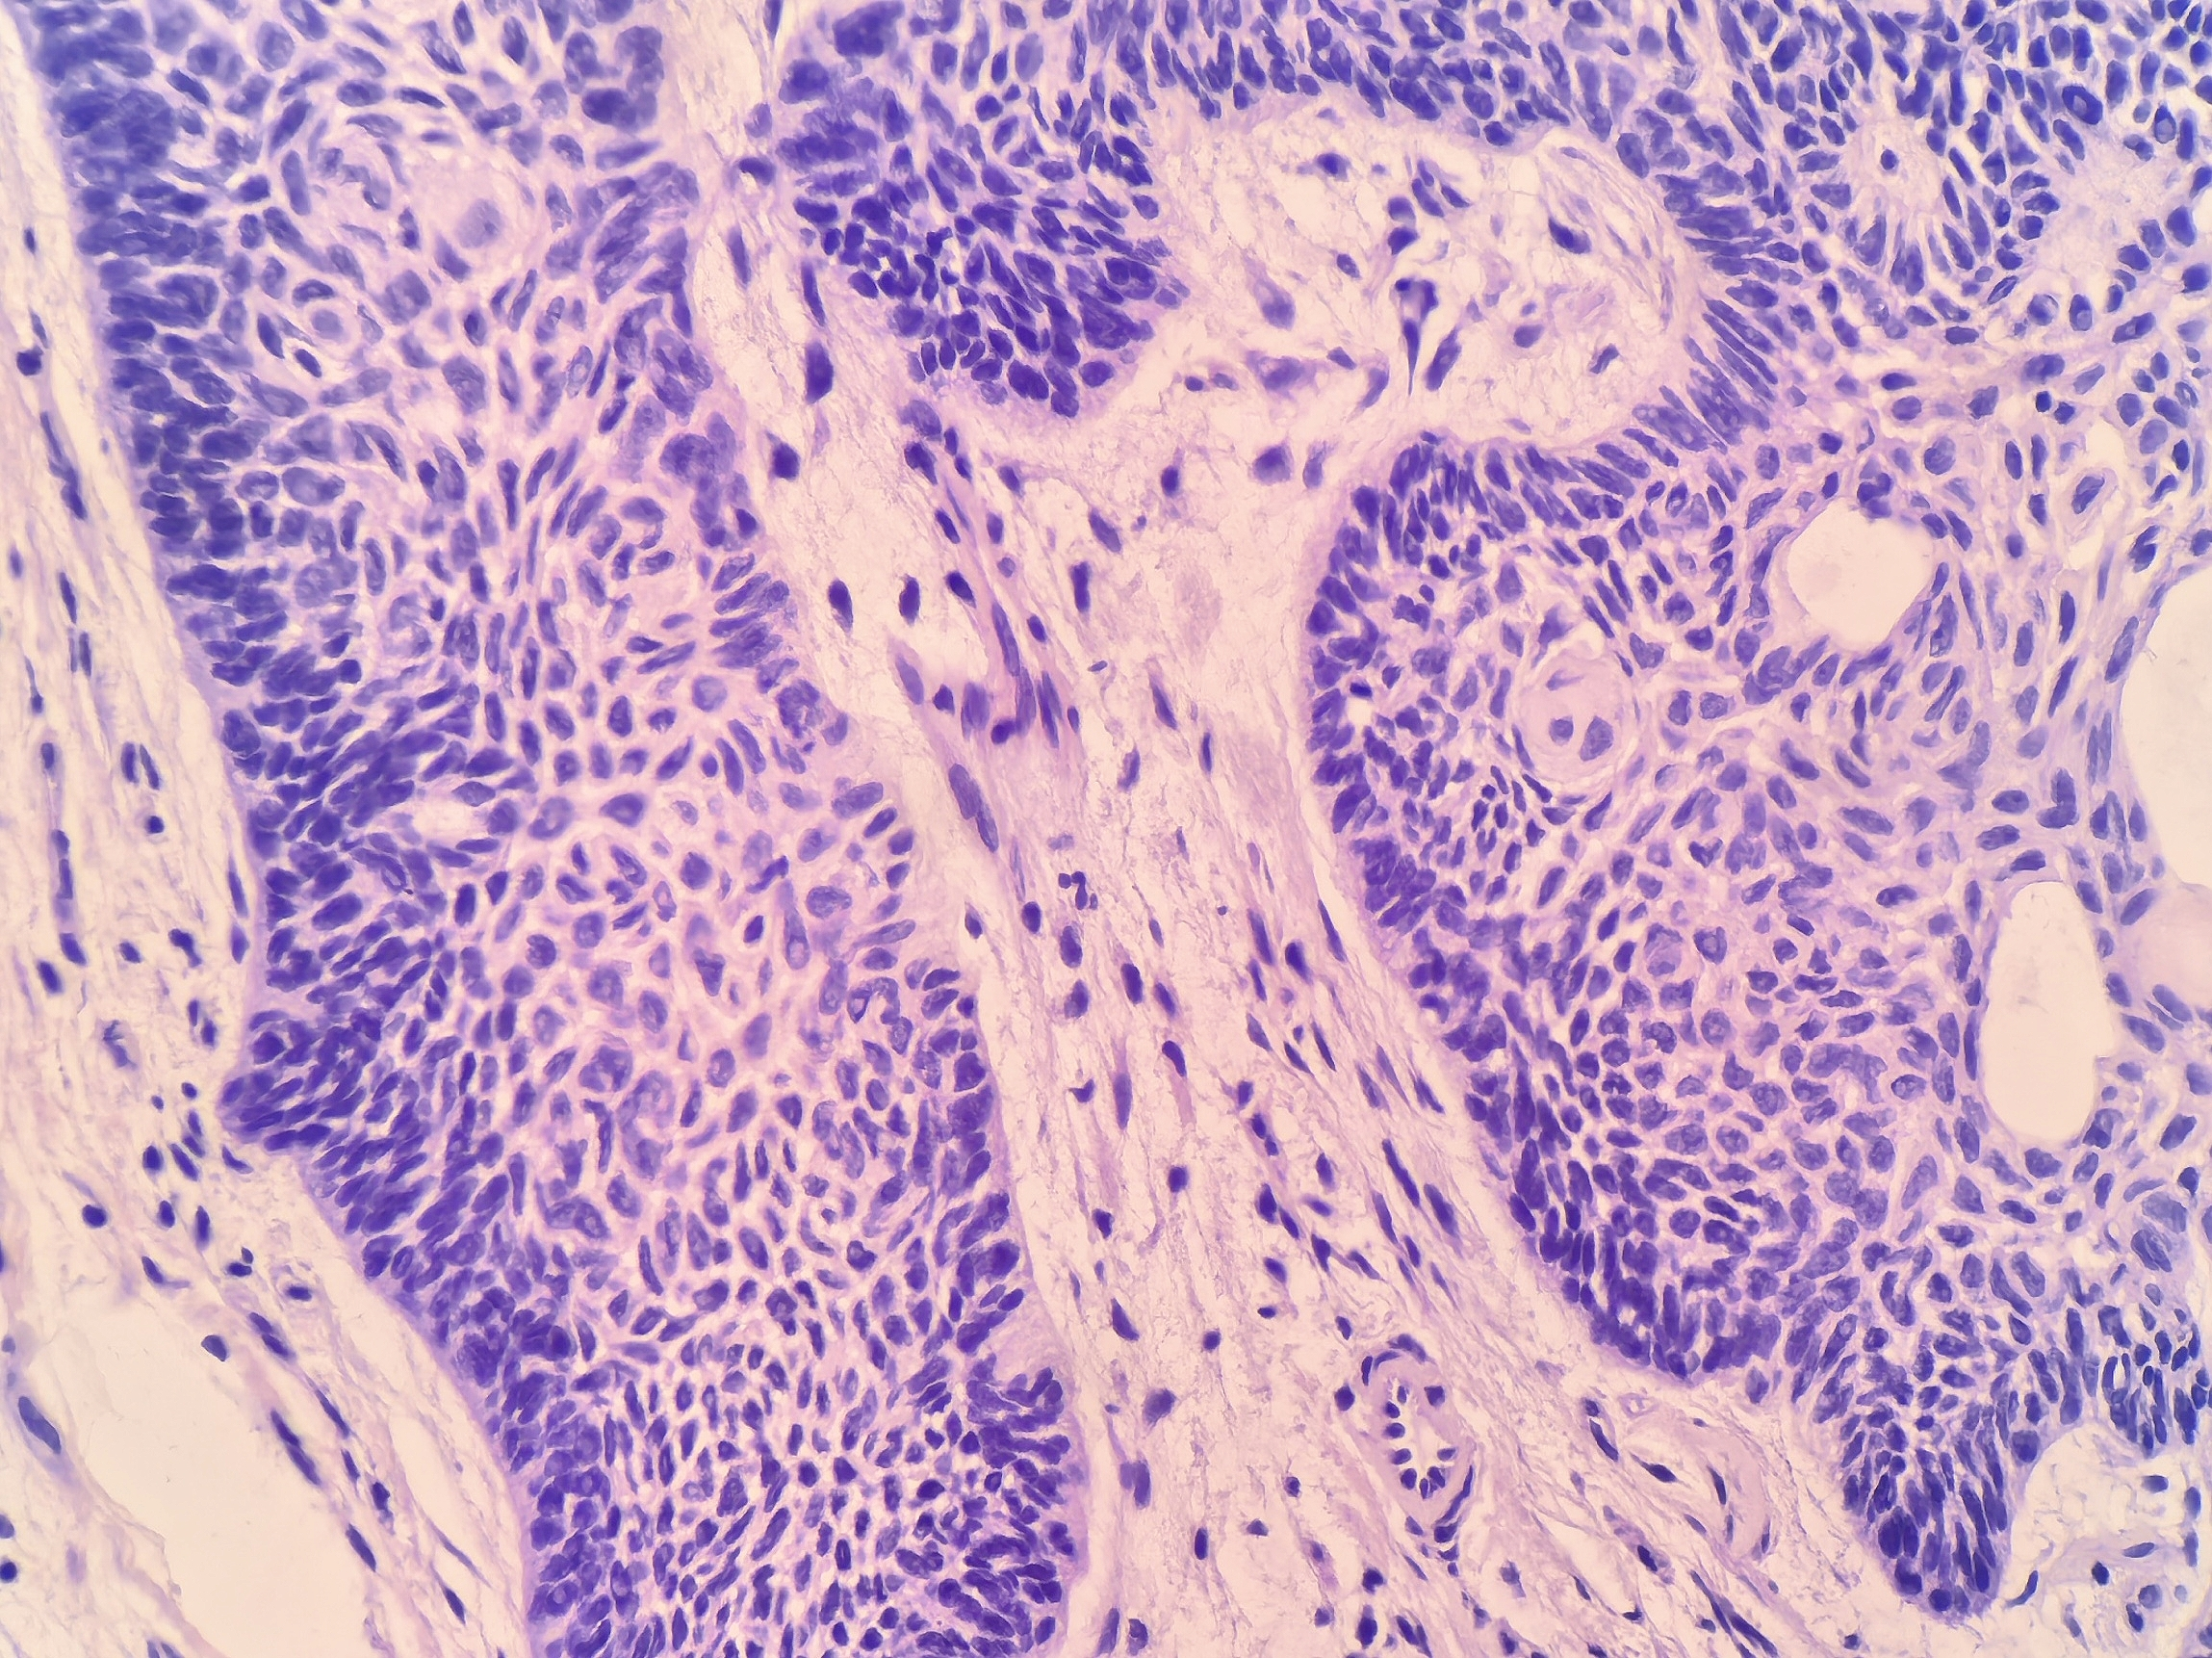

高倍镜下,肿瘤细胞呈基底样,形态较一致。肿瘤细胞团周边细胞呈特征性栅栏状排列(图3、4)

胞核卵圆形、深染,染色质细腻,核仁不明显,胞浆稀少。核分裂象罕见。巢团与周围间质间可见收缩裂隙(图5)。